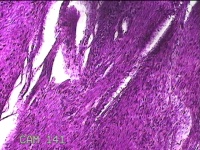

子宫肌瘤

性别

女

年龄

41岁

临床诊断

子宫肌壁间肌瘤

一般病史

发现子宫肌瘤4年余。

标本名称

大体所见

灰白色圆柱形条索状组织10.5x7x1.3㎝一堆,切面均为灰白色结节状或编织状,质硬。

图2